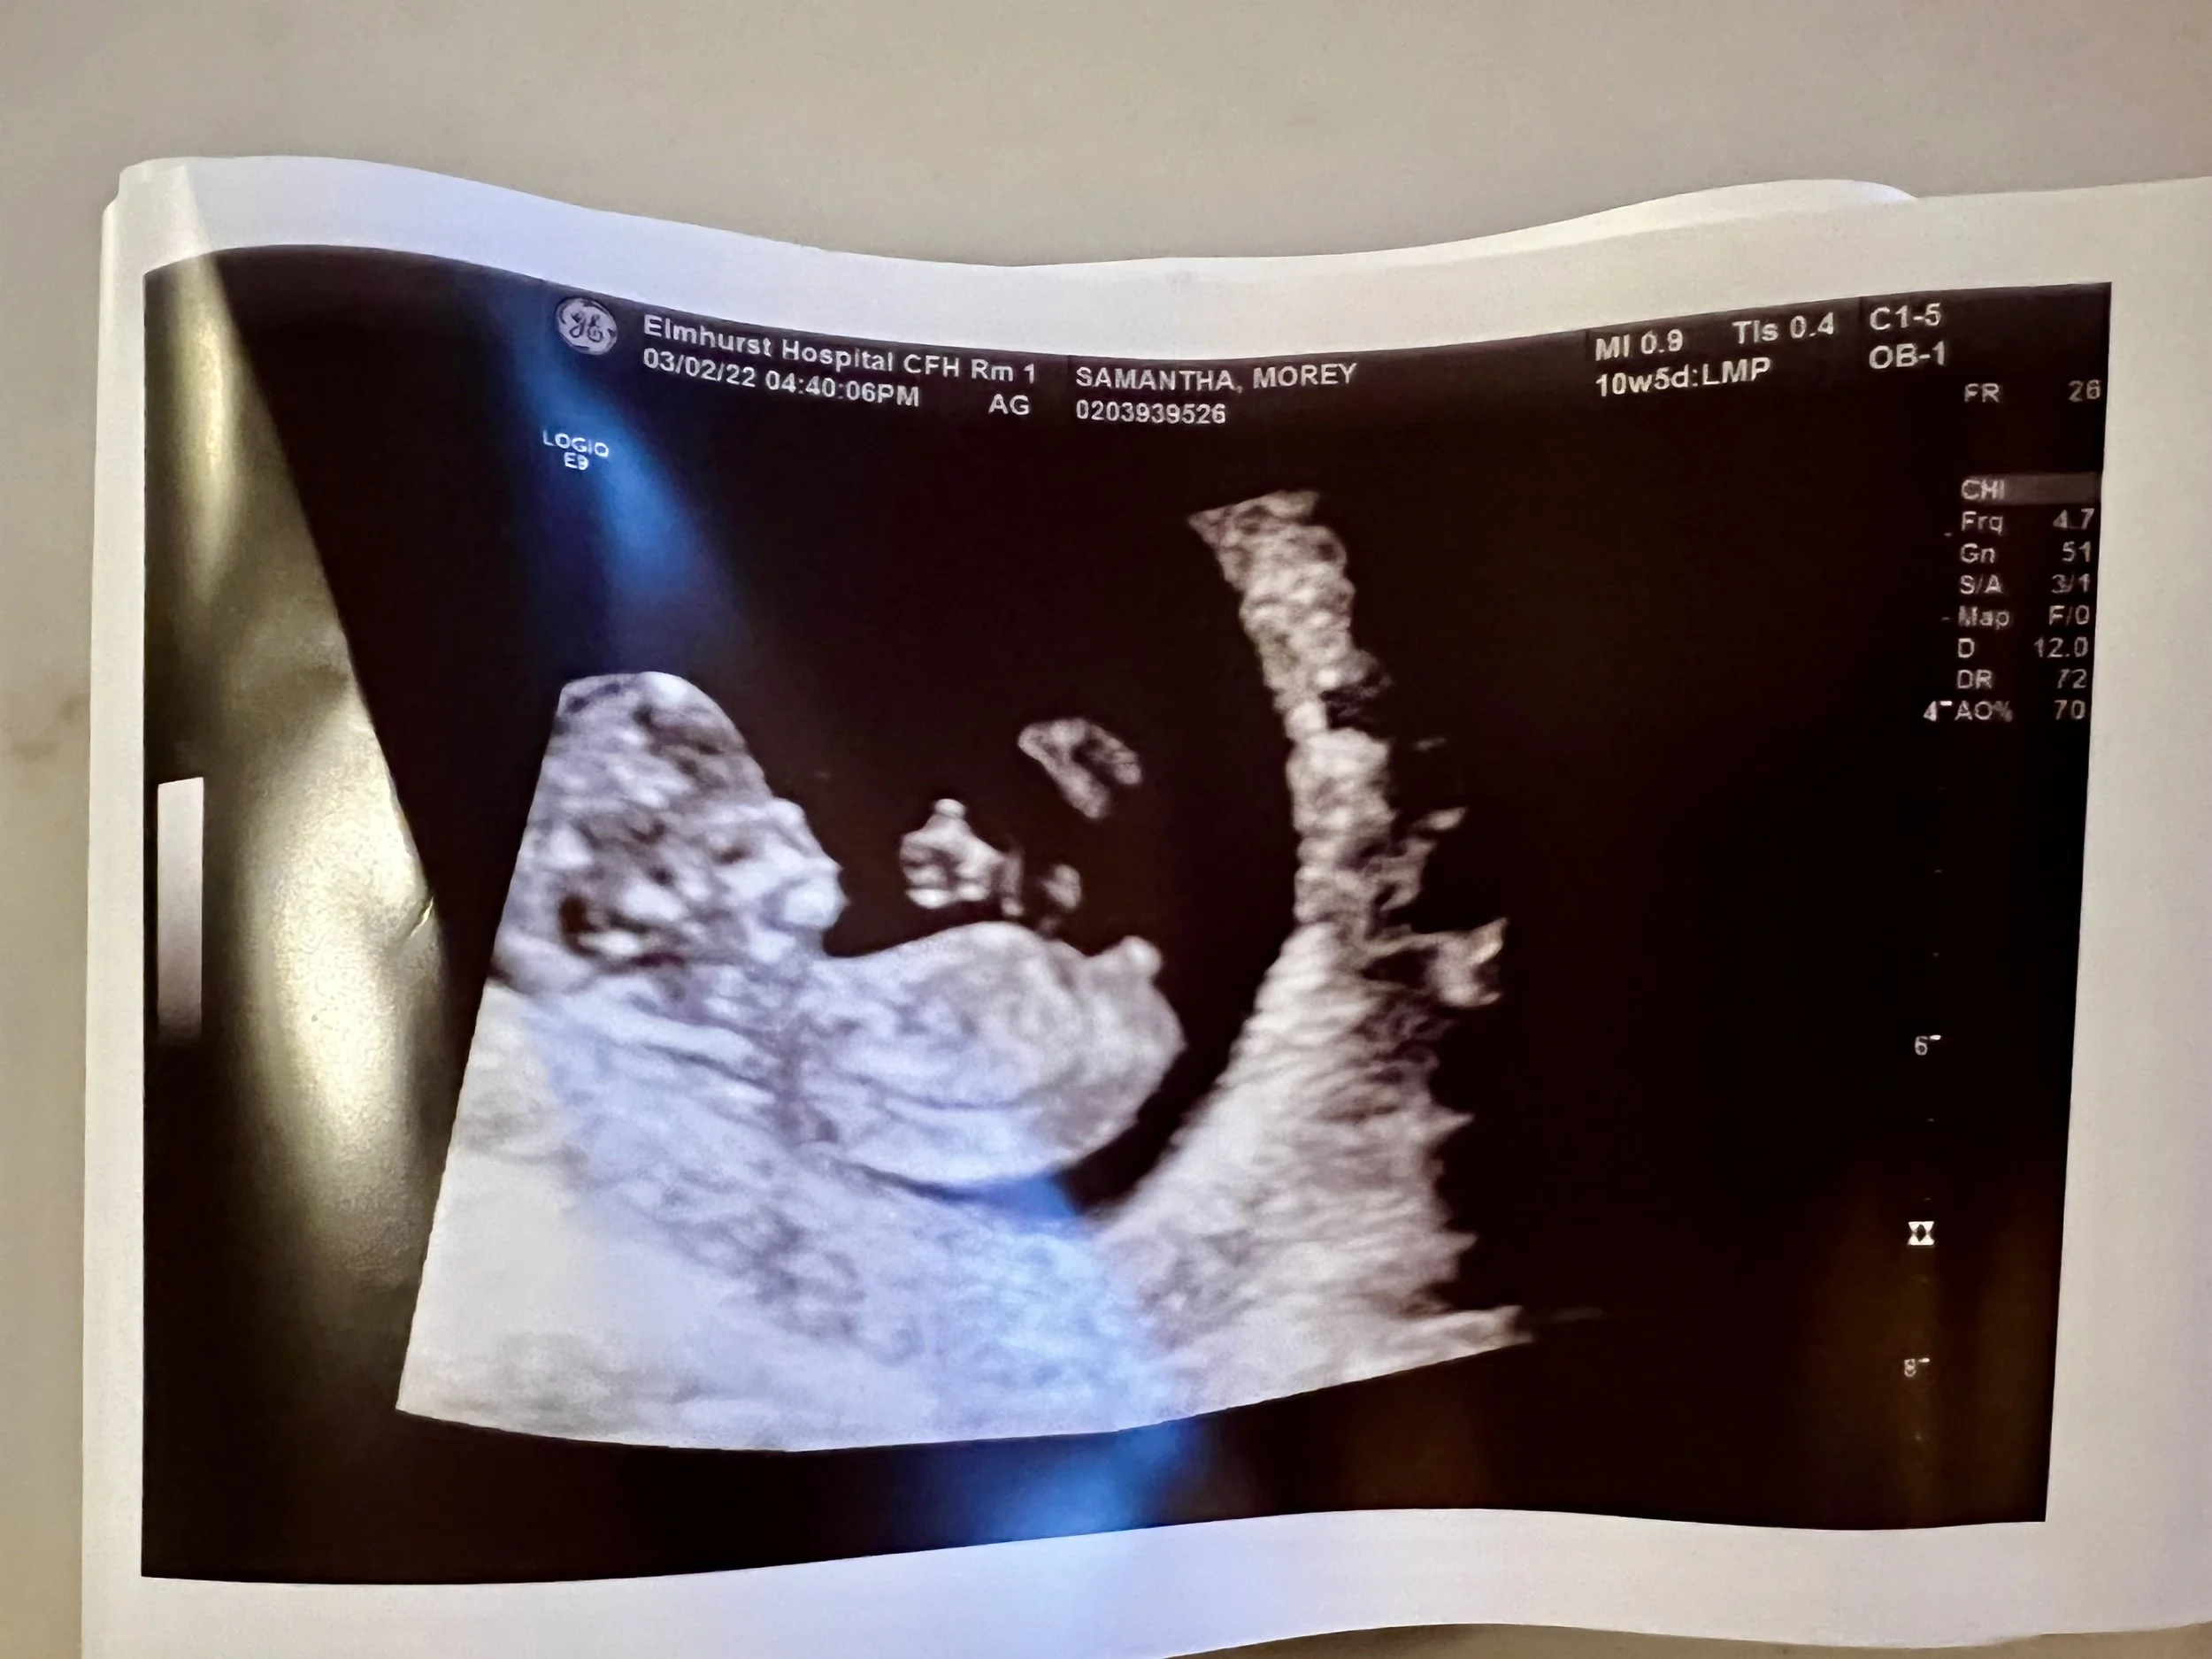

Baby’s Thumbs Up

At my first ultrasound, the tech turned the screen toward me and there was my daughter, clear as day, giving a thumbs up.

I'm not kidding. Her little hand was up in a perfect thumbs-up position, like she was saying, "Mom, I'm good. Relax."

I took it as a cosmic sign that she was doing just fine in there on her diet of pizza, tortellini, and pretzels. She didn't need me to eat kale every day or force down salmon when the thought of it made me want to vomit. She needed me to eat what I could tolerate so she could keep growing.

And she did. She was born perfectly healthy, and she's now a thriving, hilarious toddler who loves food (especially carbs, naturally).